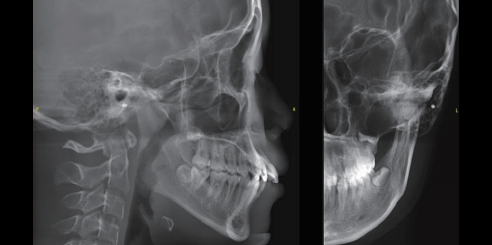

Mediciones Cefalométricas Laterales

En comparación con las radiografías cefalométricas bidimensionales tradicionales, los cefalogramas laterales en CBCT pueden reflejar mejor la verdadera morfología craneofacial. Con una mayor precisión en la identificación de puntos de referencia y la medición de distancias de líneas, puede evitar la distorsión de los datos de medición del paciente causada por la superposición, la imagen borrosa y la asimetría facial de estructuras anatómicas bidimensionales.